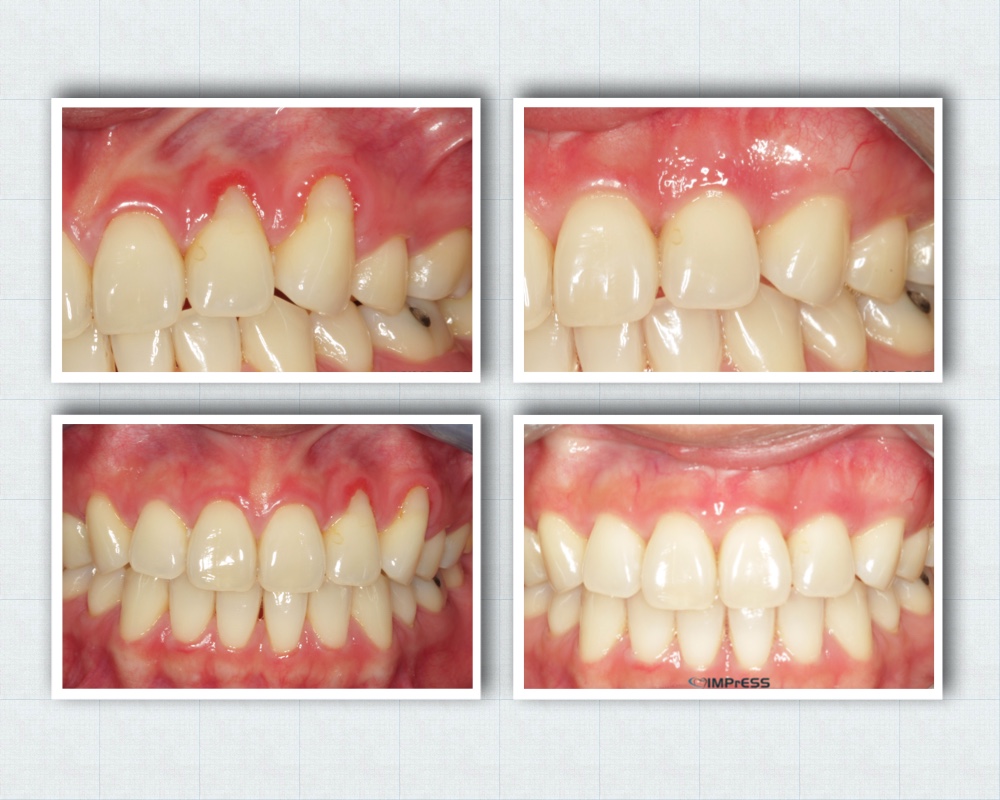

Gummy Smile Treatment- Lip Repositioning & Aesthetic Crown lengthening

Gummy Smile Treatment Esthetic Crown lengthening Dr. Noroozi IMPrESS Perio Implant Center Burnaby BC Vancouver Burnaby Periodontist

Aesthetic Crown Lengthening for Gummy Smile or Uneven Gum Line